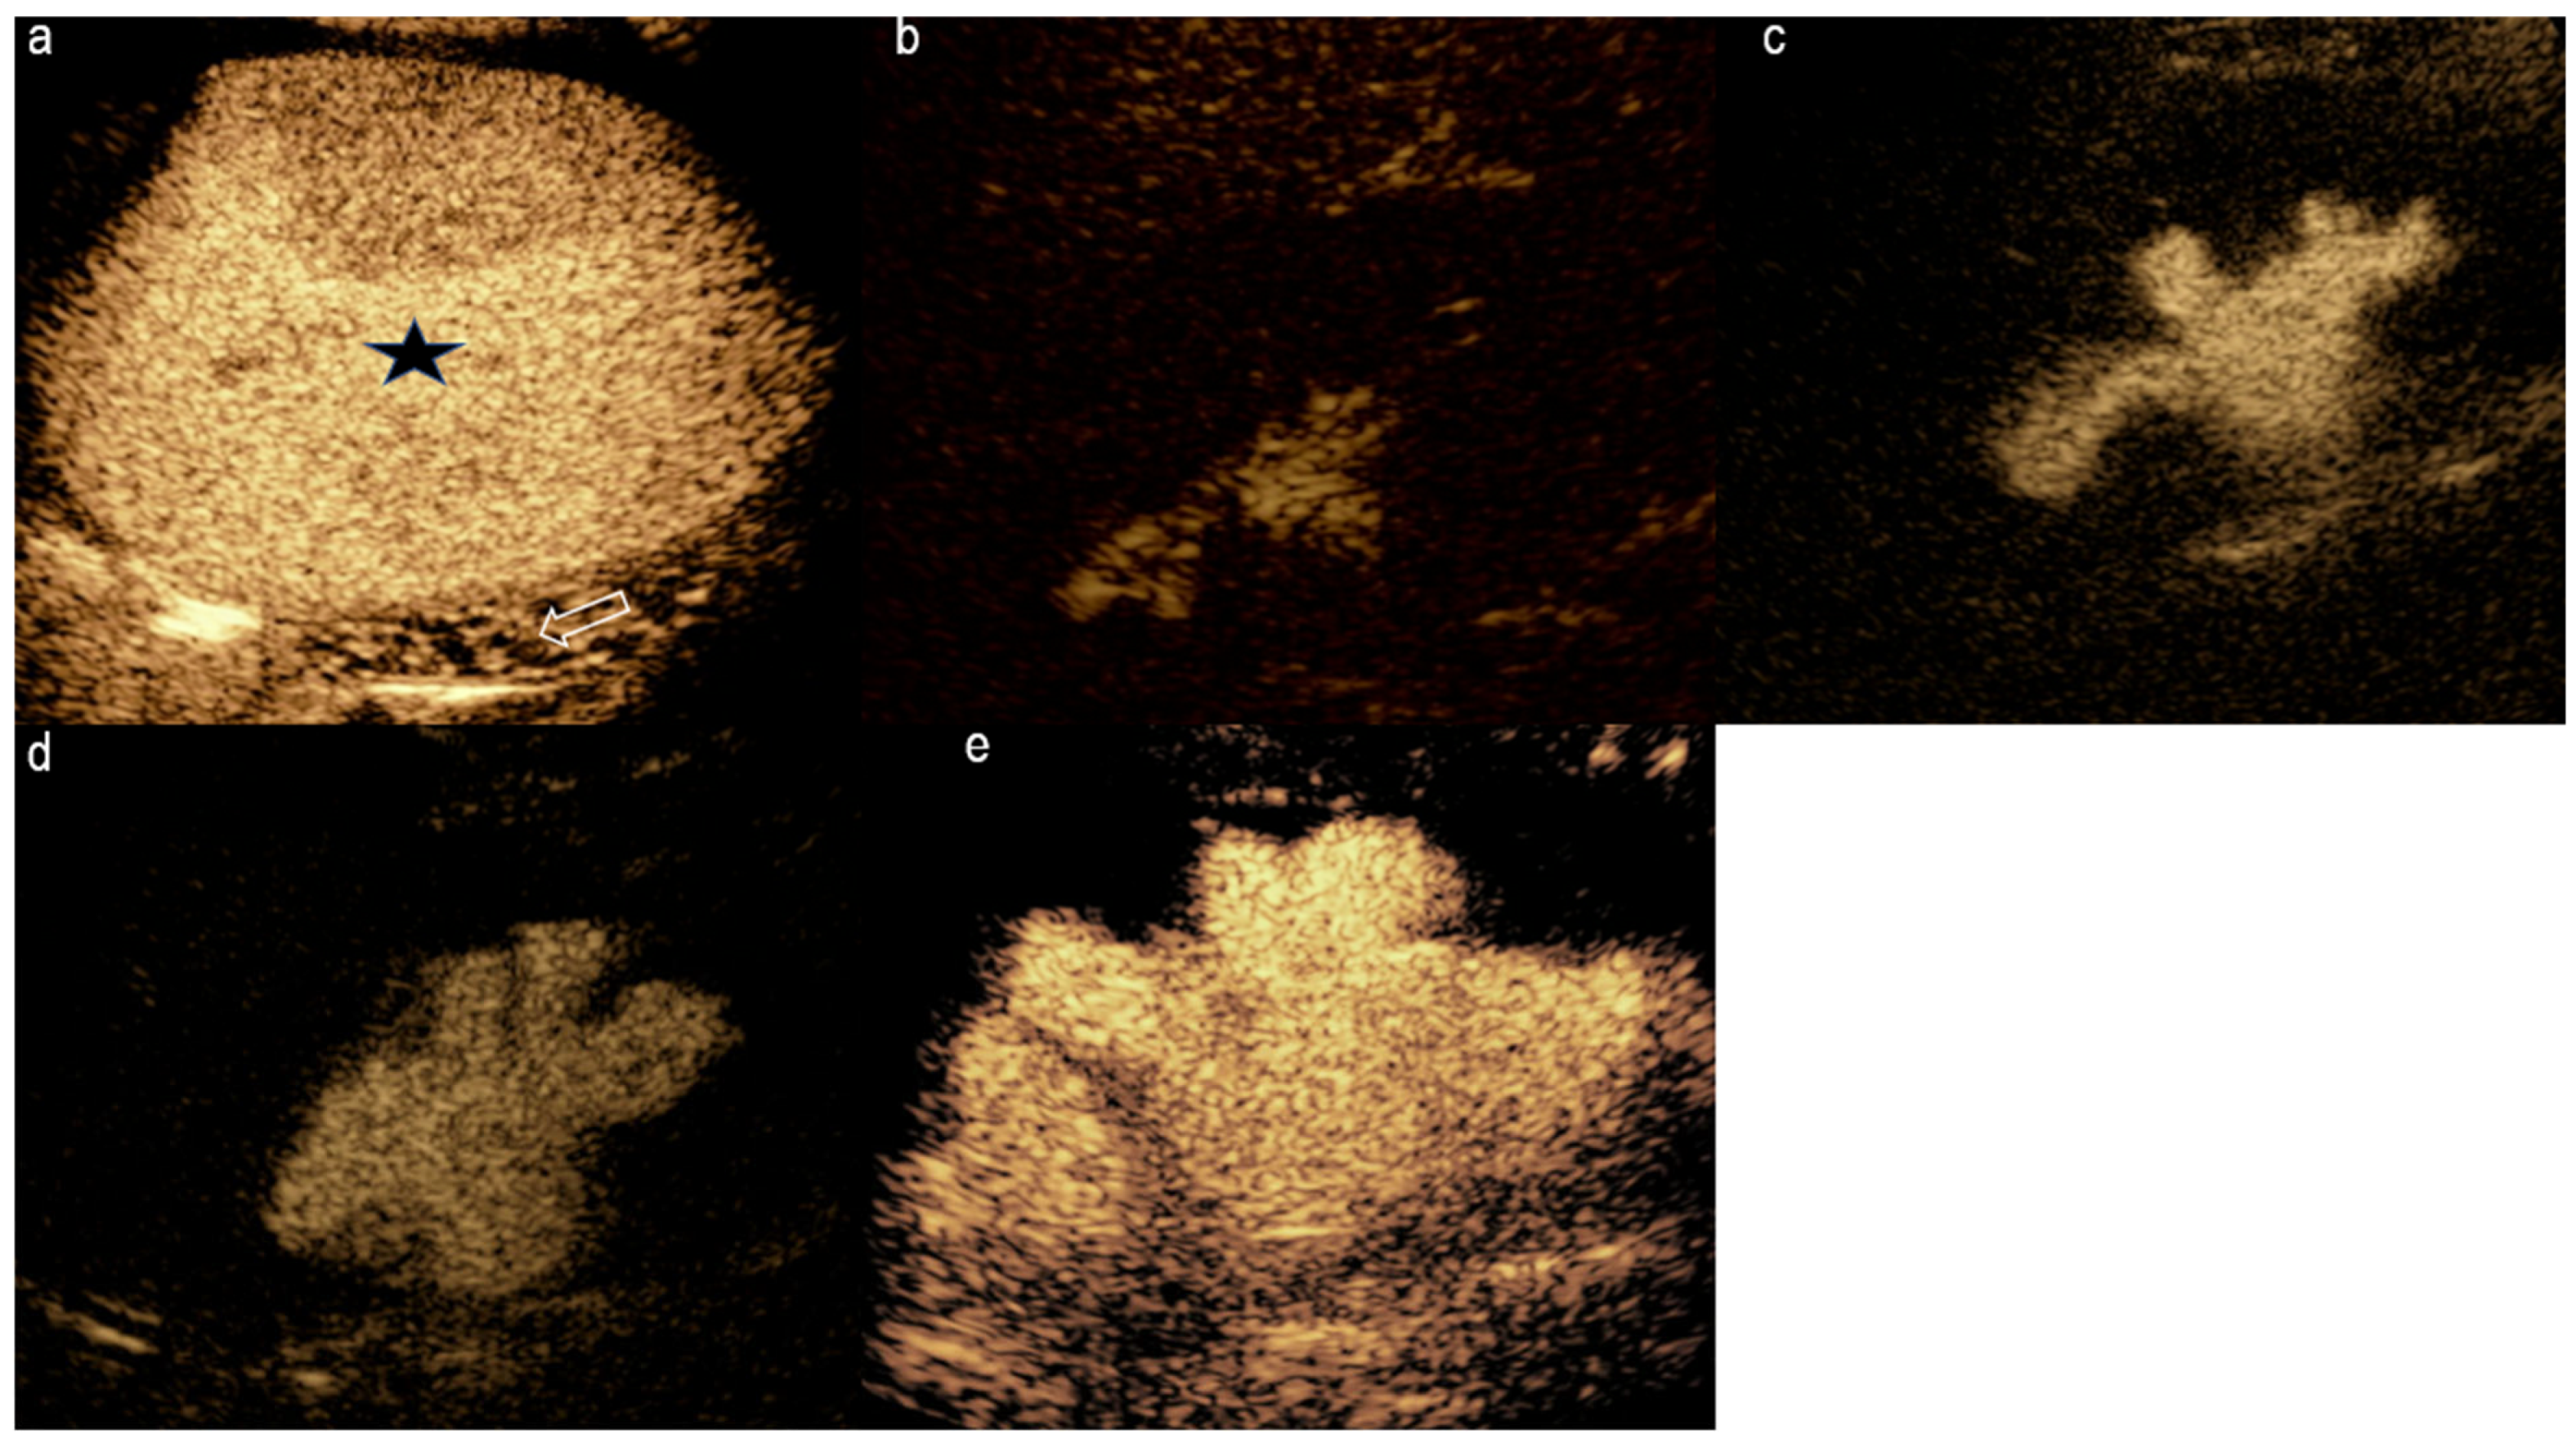

3.7. Spleen

- Catalano, O.; Sandomenico, F.; Vallone, P.; D’Errico, A.G.; Siani, A. Contrast-enhanced sonography of the spleen. In Semin Ultrasound CT MR; WB Saunders: Philadelphia, PA, USA, 2006; Volume 27, pp. 426–433. [Google Scholar]

- Reichlin, M.; Bosbach, S.J.; Minotti, B. Splenic Infarction Diagnosed by Contrast-enhanced Ultrasound in Infectious Mononucleosis—An Appropriate Diagnostic Option: A Case Report with Review of the Literature. J. Med. Ultrasound. 2022, 30, 140–142. [Google Scholar] [CrossRef] [PubMed]

- Zavariz, J.D.; Konstantatou, E.; Deganello, A.; Bosanac, D.; Huang, D.Y.; Sellars, M.E.; Patel, N.; Alhasan, R.; Westwood, M.; Sidhu, P.S.; et al. Common and uncommon features of focal splenic lesions on contrast-enhanced ultrasound: A pictorial review. Radiol. Bras. 2017, 50, 395–404. [Google Scholar] [CrossRef]

- Radcliffe, C.; Tang, Z.; Gisriel, S.D.; Grant, M. Splenic abscess in the new millennium: A descriptive, retrospective case series. Open Forum. Infect Dis. 2022, 9, ofac085. [Google Scholar] [CrossRef] [PubMed]

- Roman, A.; Iancu, C.; Andreica, V.; Socaciu, M.; Anton, O.; Sechel, R.; Pop, D.; Mera, M.; Muresan, M.; Zaharie, F.; et al. Splenic cystic lymphangioma with atypical ultrasound findings. J. Med. Ultrason. 2016, 43, 99–105. [Google Scholar] [CrossRef]

- Stang, A.; Keles, H.; Hentschke, S.; von Seydewitz, C.U.; Dahlke, J.; Malzfeldt, E.; Schneider, G.; Bücker, A.; Forsting, M.; Huppertz, A.; et al. Differentiation of benign from malignant focal splenic lesions using sulfur hexafluoride-filled microbubble contrast-enhanced pulse-inversion sonography. AJR Am. J. Roentgenol. 2009, 193, 709–721. [Google Scholar] [CrossRef]

- Lei, Y.; Huang, Q.; Li, X.; Zheng, X.; Liu, M. Characteristics and survival outcomes of primary splenic cancers: A SEER population-based study. Medicine 2022, 101, e28539. [Google Scholar] [CrossRef] [PubMed]

- Ballestri, S.; Lonardo, A.; Romagnoli, D.; Losi, L.; Loria, P. Primary lymphoma of the spleen mimicking simple benign cysts: Contrast-enhanced ultrasonography and other imaging findings. J. Med. Ultrason. 2015, 42, 251–255. [Google Scholar] [CrossRef]

- Sutherland, T.; Temple, F.; Hennessy, O.; Lee, W.-K. Contrast-enhanced ultrasound features of primary splenic lymphoma. J. Clin. Ultrasound 2010, 38, 317–319. [Google Scholar] [CrossRef]

- Omar, A.; Freeman, S. Contrast-enhanced ultrasound of the spleen. Ultrasound 2016, 24, 41–49. [Google Scholar] [CrossRef]